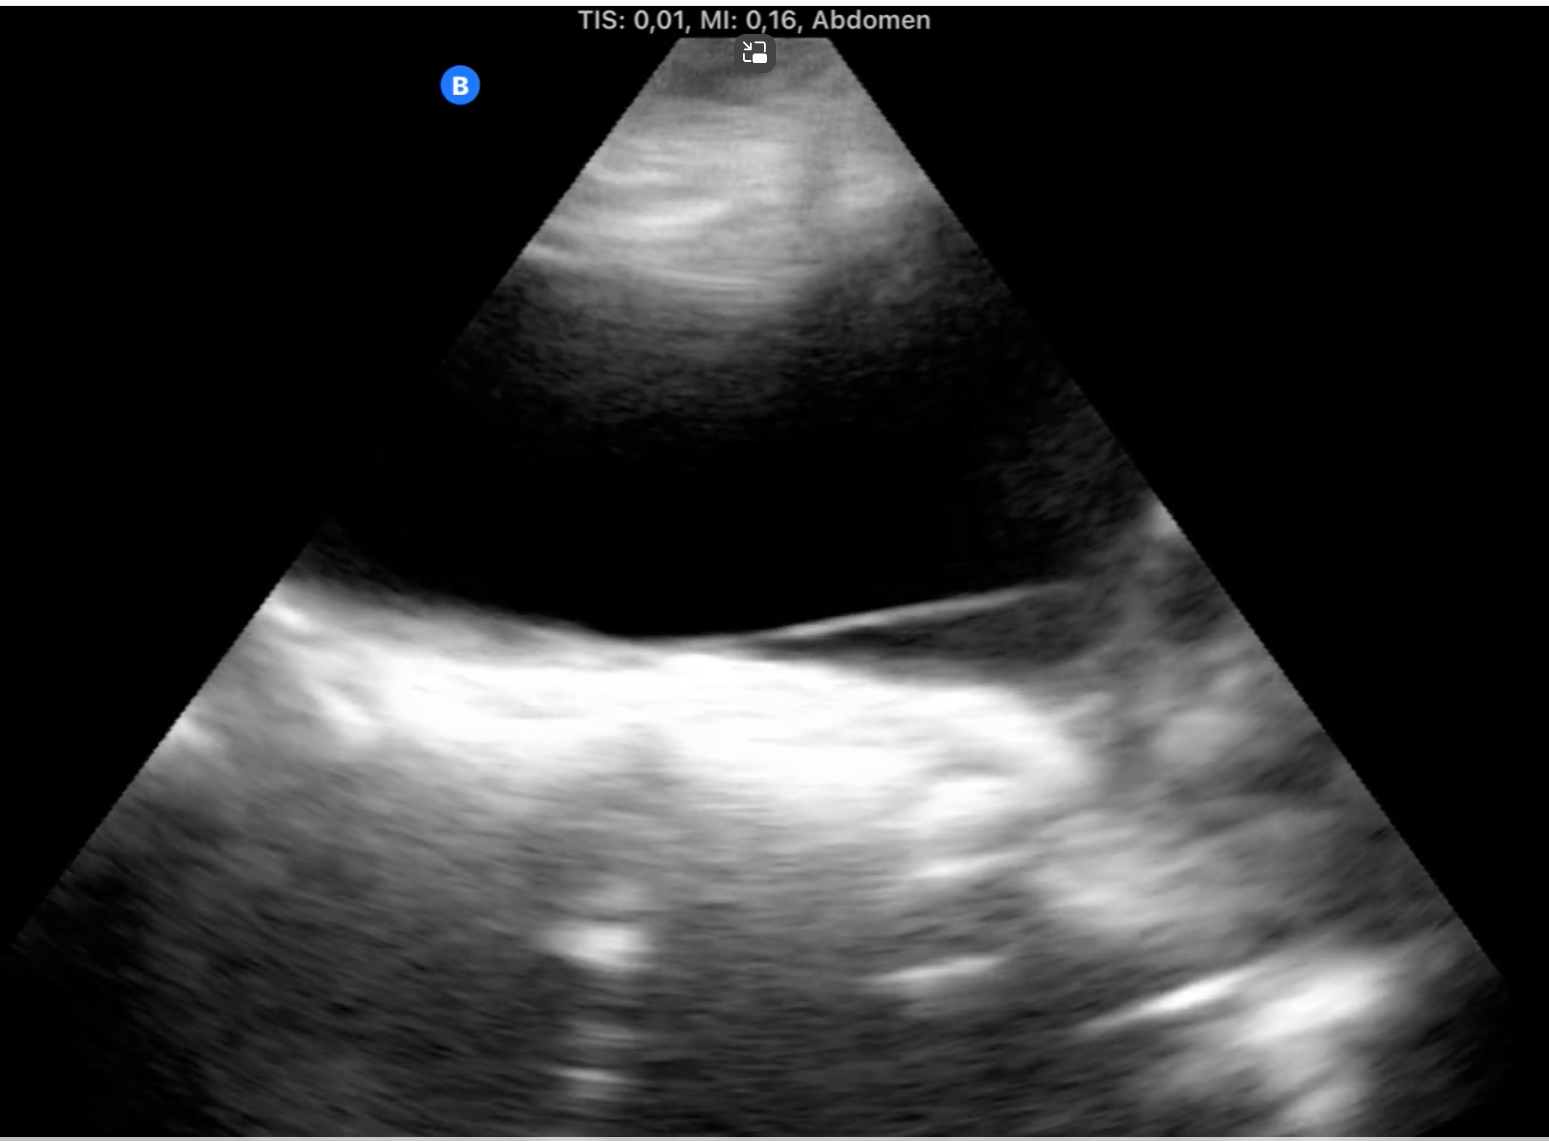

Mujer de 72 años en situación de cuidados paliativos por adenocarcinoma endometrial con sintomatología de obstrucción intestinal: implante peritoneal quístico de 8.7cm que le produce dilatación de estómago.